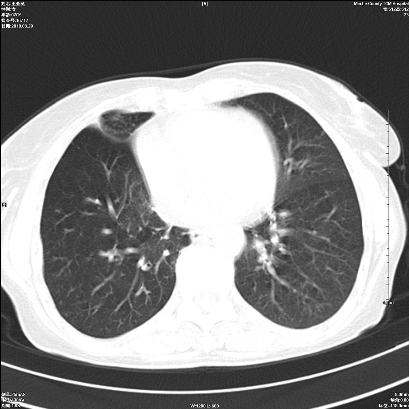

右肺上叶支气管开口阻塞,上叶呈不均匀致密影,右肺中下叶内见斑片状密度增高影,上叶见钙化点,纵隔内见钙化淋巴结,桶状胸,右下肺动脉增粗,残根征,意见:1.右肺中心性肺癌;2.右肺陈旧性结核;3.肺心病。

考虑右肺中心型肺癌并上叶不张

1)考虑右肺中央型肺癌伴右肺上叶肺不张,右肺门淋巴结转移;建议行支纤维镜检查。2)右肺中叶、下叶及左肺上叶舌段感染性病变。3)肝内多发低密度影,不排除转移瘤可能;建议行ct增强扫描检查。

ct所见:右肺上叶肺不张,呈软组织密度影向肺门区聚拢,其内可见含气段支气管及细支气管影,病灶内尚可见钙化结节。右肺上叶支气管狭窄,段支气管壁可见钙化。右肺下叶背段、右肺中叶见不规则小片絮状影及纤维条索影,形态较僵硬。右肺中叶胸膜旁可见多个小结节影。纵膈内见钙化淋巴结。

分析:右侧胸廓及右肺体积缩小,说明病变时间比较长了,应该是有数年的时间了,如果是短期内出现的肺不张,只会引起纵膈向患侧移位,而不会引起胸廓的塌陷。不张的肺组织内可见含气支气管影,说明右肺上叶支气管没有完全中断,只是狭窄。右肺中叶、下叶散在不规则病灶,部分呈纤维化改变。纵膈内的淋巴结大部分钙化。因此,本例给我的感觉良性病变的可能是大。

结论:考虑右肺上叶支气管内膜结核合并右肺上叶肺不张;右肺中叶、下叶陈旧性肺结核改变。